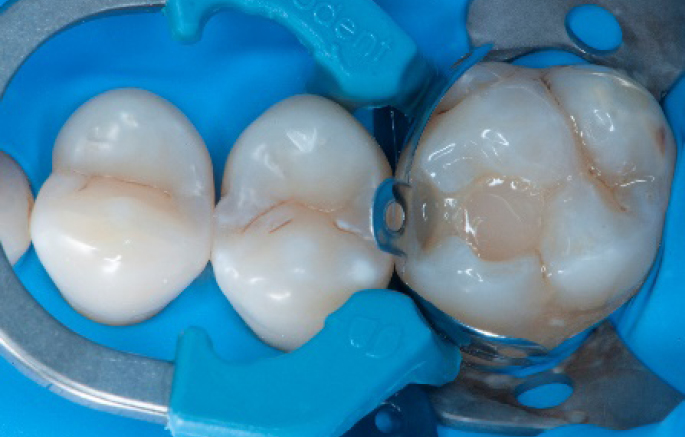

Step 10:

The situation after the application of SDR® flow+ material.

Step 11:

Occlusal surface restored using Spectra ST4 composite in shade A2.